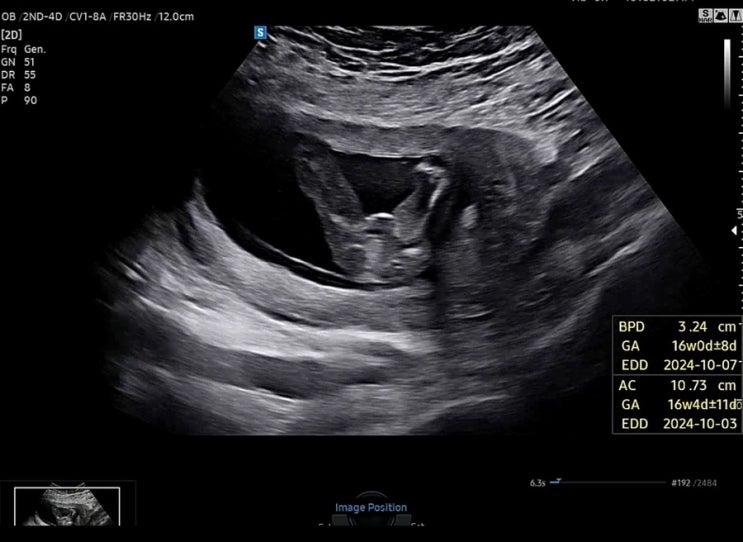

24.4.22 16주0일차에 2차 기형아검사를 받고 24.4.29 딱 일주일이 지난 17주0일차에 병원에서 전화가 왔다....

[임신기록]임신13주~16주까지

#임신초기증상 12주까지만 해도 울렁거렸던 입덧이 13주 접어드니 눈에 띄게 괜찮아지고 입덧시기에도 먹기...